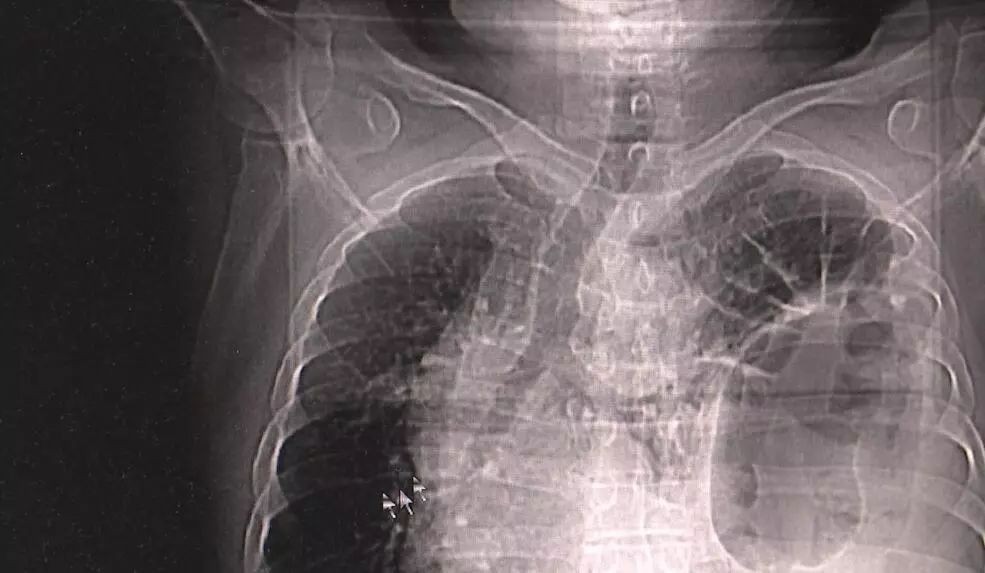

▲男子發生嚴重器官位移,讓醫師也大吃一驚。(圖/翻攝自杭州網/下同)

杭州電視台報導,浙江大學醫學院附屬第二醫院腹部腔鏡外科主任王躍東表示,正常情況下,大腸都會在橫膈膜的下方,但郭姓患者的胸部X光和電腦斷層顯示,他胸腔和腹腔間的膈肌出現一手掌大小的破洞,導致他的腸胃透過破口轉移到胸腔。醫師還發現,患者的胃不只大移位,還穿過洞口形成折疊形狀。